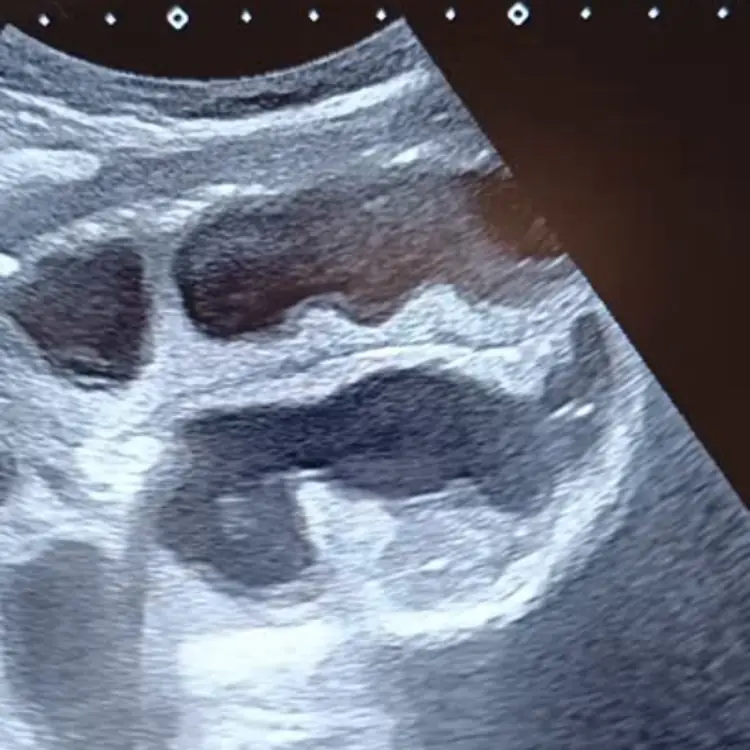

Globe ou obstruction : trancher en urgence.